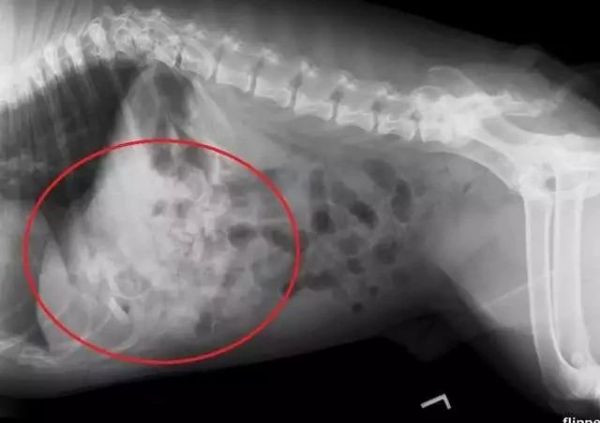

“偷吃了19个安抚奶嘴差点丢了狗命”

另一位铲屎官家的英斗从4月份开始经常出现呕吐现象,但一直没有找出原因。刚开始主人以为吃坏肚子了,从宠物诊所拿了一些药......没有起到丝毫作用。

原本活泼好动的狗子,变得嗜睡、无精打采,甚至拒食。主人这才意识到情况有些严重,带着狗狗到宠物医院进行了检查。

在X光照射下才终于查明病因,狗狗胃中塞满了异物。

医生立即安排了手术,结果让人大吃一惊:竟从狗子的胃里取出了19个安抚奶嘴。主人从来没有注意到安抚奶嘴居然被狗狗偷吃了这么多。